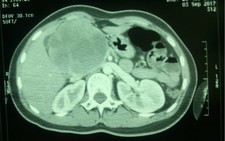

TS.BS Đoàn Tiến Mỹ - trưởng khoa gan mật tụy - cho biết thông qua hình ảnh học, các bác sĩ chẩn đoán khối u to xâm lấn vùng tụy, chiếm hết vùng bụng phải, gây hoại tử trung tâm, chèn ép tĩnh mạch cửa, chèn ống mạch, tĩnh mạch gan...

"Khối u đã dính vào nhiều tĩnh mạch, các bác sĩ phải mất 10 tiếng phẫu thuật, cắt hoàn toàn khối tá tụy, lấy ra khối u có kích thước 20cm, nặng 2,2kg, có thể nói là lớn nhất từ trước đến nay mà chúng tôi từng gặp," bác sĩ Mỹ nói.